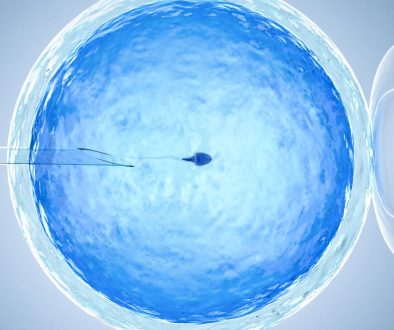

هناك العديد من الخيارات العلاجية المتاحة، مثل الأدوية المحفزة للإباضة أو تقنيات الإنجاب المساعدة كالتلقيح الصناعي. التحدث إلى الطبيب يمكن أن يساعد في تحديد الخيار الأفضل.